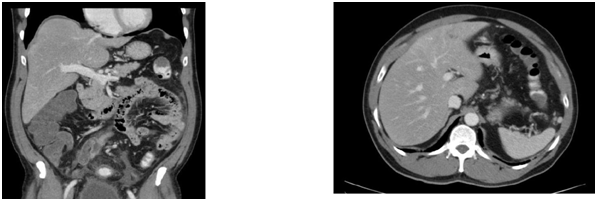

The CT thorax and CT pulmonary angiogram showed marked pulmonary infiltrates and thrombi. There was a thombus in the segmental right lower lobar pulmonary area, with an infracted region in the right lung base. There was also another thrombus in the anterior segmental branch of the left lower lobe pulmonary artery. Subsequently, the patient suffered from opthalmoplegia due to stroke in the ward. The MRI/MRA revealed acute infarcts in the left cerebellum, occipital lobe and left medial longitudinal fasciculus. He also developed gut vasculitis and a perforated transverse colon (Figure 3) (Figure 4). The findings on CT abdomen and pelvis were consistent with that of a small/medium vessel vasculitis. Multifocal ischemic colitis was seen involving the right lateral and posterior walls of the rectum as well as the inferior wall of the mid transverse colon with suggestion of perforation on both sides. The superior rectal artery was thrombosed as well. The patient then underwent emergency laparotomy with resection of small bowel and stoma creation. Post-operatively recovered well and was discharged two weeks after. Currently he is on follow up with rheumatologist, neuroopthalmologist and general surgeon (Figure 5).

Figure 3 CT abdomen and Pelvis.

1. NON- specific long segment thickening of the rectal wall; soft tissue and extensive fat stranding are seen in t he mesorectum. Omental fat stranding is most promi nent in the upper abdomen abutting the anterior wall of transverse colon; thickening of the anterior transverse colon wall abutting the omental stranding.

2. 0.6cm splenenculi are seen in close relation to the anterior pole of the spleen.

3. A 1.6x1.2cm enlarged celiac node is noted.

4. Small volume, but round lymph nodes are seen along the inferior mesenteric artery and the para -aortic region, the largest in the para- aortic region measures 0.9x0.8cm.